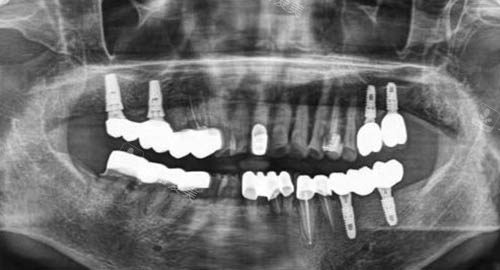

多颗牙齿种植ct

问:贝格口腔的收费情况如何呢?

答:贝格口腔的收费非常透明,没有任何套路。

在治疗前,医生会详细地向患者介绍治疗方案以及对应的费用,让患者清楚每一项收费的用途。

医院还会根据不同的诊疗项目制定合理的价格标准,不会出现乱收费的现象。